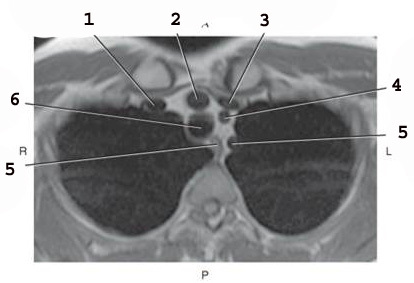

1

Left brachiocephalic vein

2

Braciocephalic Artery

3

sternum

4

L Common carotid A

5

Left subclavian Artery

6

Esophogus

7

Trachea

8

RT brachiocephalic vein (page 325)